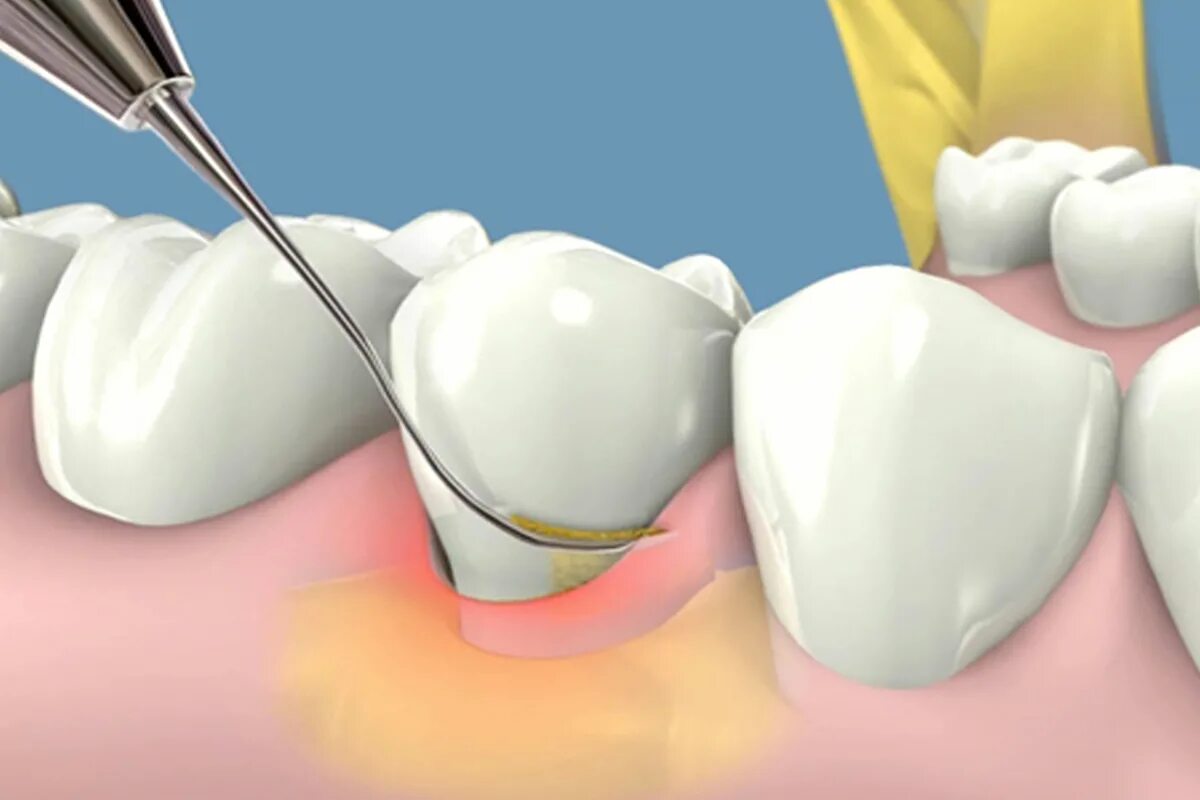

Зубной карман